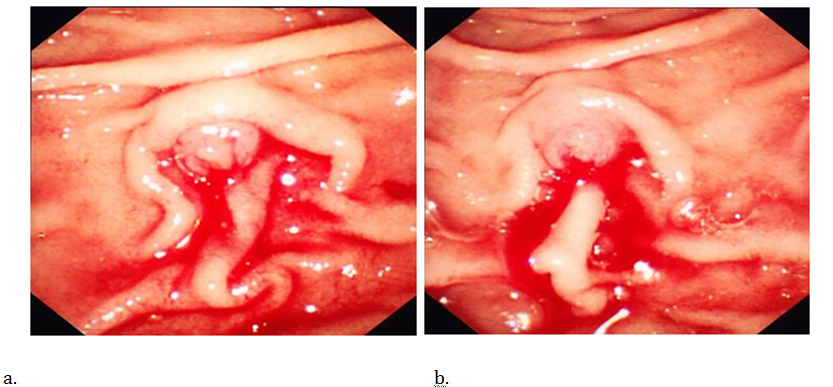

In October 2012 he was admitted again with malena & low haemoglobin. OGD was normal and CT angiogram showed no residual pseudo-aneurysm. RBC scan showed bleeding from region of duodenum/jejunum. Single balloon enteroscopy was performed which showed clot in second part of duodenum and blood oozing from the ampulla Figure 2 (A&B). MRCP confirmed beaded dilation of pancreatic duct with normal biliary tree & liver. Since CT had shown some splenic varices with splenomegaly a liver biopsy was conducted which showed no evidence of cirrhosis and the varices were thought to be secondary to splenic vein thrombosis. Subsequently a repeat CT angiogram did not show any recurrence of pseudo-aneurysm. His LFT’s were always normal and so was his biliary anatomy. A diagnosis of Hemosuccus pancreaticus was made and his was referred to the regional hepato-biliary centre.

Figure 2 A & B Endoscopic view of the ampulla of vater showing blood oozing from the ampulla with no periampullary ulcer.